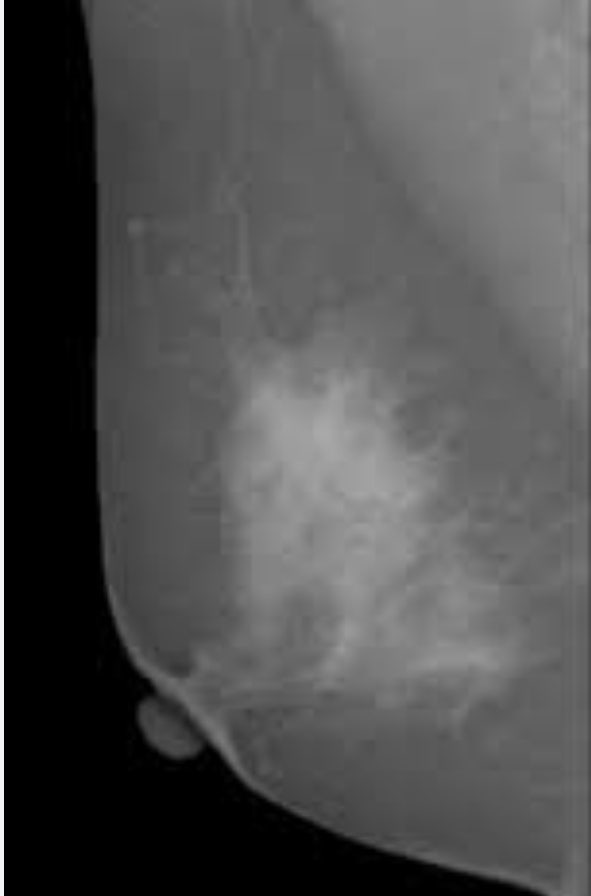

유방암(초기 증상 원인 예방법 호르몬 치료 주의 법은?)

유방암에 대해서 이야기를 해보자면, 주로 여성들에게 많이 생기는 암 중에 하나 이다. 물론 남성도 걸릴 ...